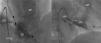

Case 2We present the case of an 80-year-old woman implanted with a permanent VDD pacemaker in 2001 for symptomatic conduction tissue disease, who underwent generator replacement due to battery depletion in February 2009. In August 2010 she went to the emergency department with a clinical setting of exertional dyspnea (NYHA class III/IV), orthopnea, edema, predominantly right quadrant abdominal pain, asthenia and anorexia, progressively worsening over the previous two months. Physical examination showed jugular vein distension, facial cyanosis, generalized edema, hepatomegaly and rapid irregular peripheral pulse; pulmonary auscultation revealed no signs of congestion, while cardiac auscultation revealed soft heart sounds and an aortic mid-systolic murmur and a low-frequency diastolic murmur at the left sternal border. The electrocardiogram showed atrial fibrillation with controlled ventricular rate alternating with ventricular pacemaker rhythm. The chest X-ray revealed cardiomegaly, obliteration of the costophrenic angles and a redundant loop of the ventricular lead at the level of the tricuspid valve apparatus, with no other significant abnormalities (Figure 3A). Laboratory tests detected slight elevation of BNP and GGT but no other relevant alterations. Echocardiography revealed thickened TV leaflets and the ventricular lead adhering to the valve and subvalvular apparatus, severely limiting opening (peak and mean gradient of 15 and 10mmHg, respectively, and estimated functional area of 0.6cm2) (Figure 4), aortic sclerosis and a moderate pericardial effusion at the left ventricular free wall (1.6cm) and large effusion at the right ventricular wall (2.4–2.1cm), with slight right ventricular diastolic collapse (Figure 3B). Right heart catheterization showed malpositioning of the pacemaker lead at the level of the TV, which was deformed, with reduced and eccentric opening (mean gradient of 11mmHg) (Figure 5). Left heart catheterization revealed a deformed and calcified aortic valve (maximum ventricular–aortic gradient of 13mmHg with preserved left ventricular function – ejection fraction 62%), and coronary atherosclerosis with wall calcification but no evidence of significant stenosis.

(A) Chest X-ray showing cardiomegaly, obliteration of the costophrenic angles and a redundant loop of the ventricular lead at the level of the tricuspid valve apparatus; (B) B-mode echocardiogram showing moderate pericardial effusion at the left ventricular free wall (1.6cm) and large effusion at the right ventricular wall (2.4–2.1cm).